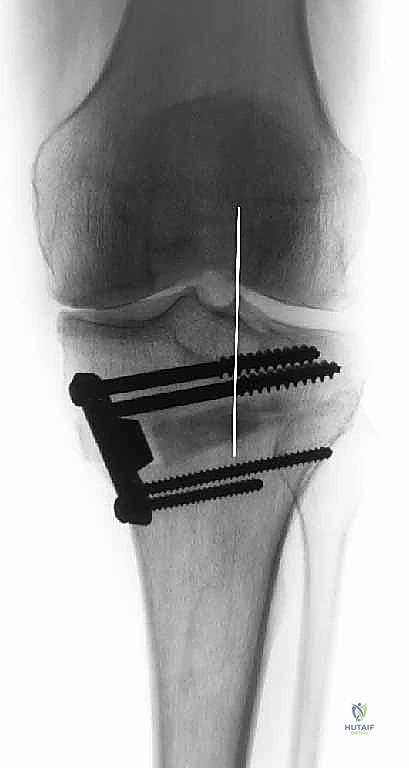

في الحالة الطبيعية الميكانيكية، يمر "محور تحمل الوزن" (Weight-bearing axis) مباشرة عبر منتصف الركبة، مما يوزع الضغط بالتساوي. ولكن، عند حدوث تقوس في الساقين (Varus Deformity)، ينزاح هذا المحور إلى الداخل، مما يضع ضغطاً هائلاً ومدمراً على الغضروف الداخلي للركبة.

هذا الضغط المستمر يؤدي إلى تآكل الغضروف بشكل أسرع من الطبيعي، مما يسبب احتكاك العظم بالعظم، وهو ما يُعرف بخشونة الركبة. هنا يأتي دور الجراحة لإعادة توجيه هذا المحور نحو الجزء الخارجي السليم من الركبة.

قبل العملية، يتم قياس زوايا الركبة بدقة متناهية. كل درجة من درجات التعديل يتم حسابها مسبقاً.

استخدام التخطيط الرقمي يضمن عدم حدوث تصحيح مفرط (Over-correction) أو تصحيح ناقص (Under-correction)، وهو ما يميز الجراح الخبير عن غيره.

4. تعديل المحور:

يتم فتح العظم تدريجياً وببطء شديد حتى الوصول إلى الزاوية التي تم حسابها في التخطيط الرقمي قبل الجراحة.